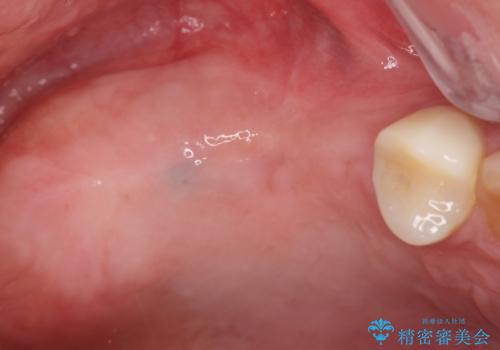

インプラント埋入時に骨の造成を、2次手術時に歯肉の凹みを整え厚みを一定にするような治療を進めていきます。

骨の造成、歯肉を整えたことで、術前山形にえぐれていた歯肉形の態はなだらかになり清掃しやすい状態へと整備することができました。